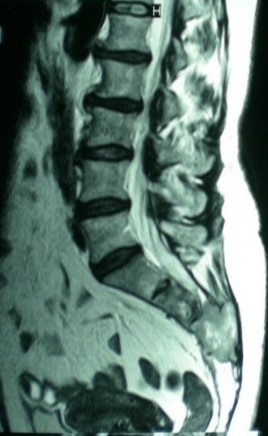

Introducción: Los tumores del sacro corresponden a menos del 7% de los tumores espinales. Prevalecen los secundarios por mieloma múltiple o carcinomas de próstata, mama, pulmón o colón. De los primarios, el cordoma es el maligno más frecuente y el tumor de células gigantes el benigno.Por su evolución, compromiso de estructuras extra óseas y la escasa respuesta a la coadyuvancia, la cirugía es el tratamiento más utilizado, la vía de abordaje y la necesidad de instrumentación dependerá del tumor a tratar.Objetivos: Los objetivos de este trabajo son: evaluar la utilización de resección parcial de sacro, analizar la técnica quirúrgica y reconocer complicaciones.Material y métodos: Cuatro pacientes con diagnóstico de tumor sacro ubicado por debajo de S1, que consulta por dolor y que las imágenes confirman la lesión. A todos se les realiza una resección en bloque por vía posterior preservando S1. Se describe la técnica.Resultados: La anatomopatológica fue: un cordoma, un tumor maligno de vaina nerviosa, un condrosarcoma y una metástasis de carcinoma prostático. Se preservo la función de S1 en todos los pacientes; uno presenta disfunción vesical permanente. Se observaron una dehiscencia de herida, una infección y fistula de líquido cefalorraquídeo. Con un seguimiento entre 6 y 24 meses todos los pacientes se encuentran libre de patología.Conclusiones: La resección parcial del sacro por abordaje único vía posterior puede ser indicada cuando la lesión comprometa desde S2 hacia distal y sin compromiso sacroilíaco. La preservación de raíces es de vital importancia para garantizar mejores resultados post operatorios y menor tasa de infección.Descargas